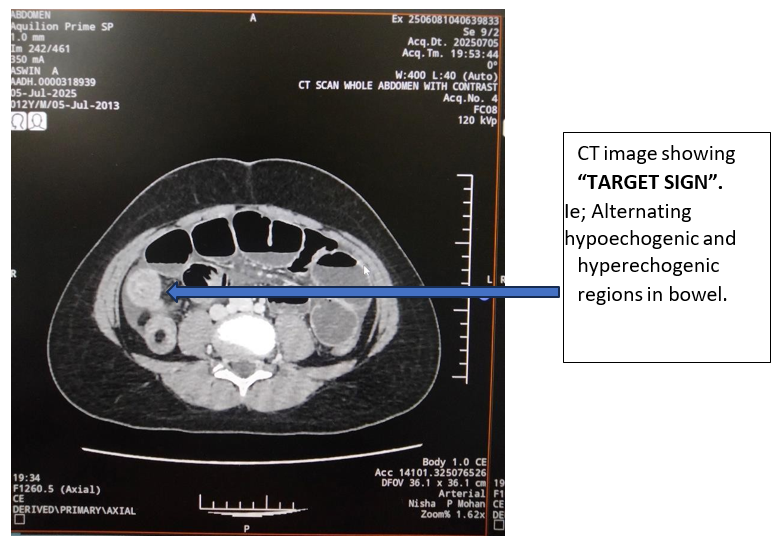

A 12-year-old male child was admitted to emergency department with complaints of abdominal pain and recurrent episodes of vomiting since 2 days. On examination, the child was conscious, oriented, afebrile and vitals were stable. On per abdominal examination, there was distention and tenderness was present over Right hypochondrium, epigastrium and umbilical regions. There was no guarding and rigidity with active bowel sounds. Initially child was kept nil per oral and kept under continuous Ryles tube aspiration. Simultaneously child was managed with IV fluids and broad-spectrum antibiotics. All routine blood investigations were done and was within normal limits. Ultrasound abdomen showed: long segment ileocecal and ileoileal intussusception at right lower quadrant region with evidence of alternating hypoechogenic and hyperechogenic regions giving classical “target sign”. Mild dilatation of proximal small bowel loops (3.2cm maxi). Since intussusception is unusual at this age, to find the lead point CECT abdomen was taken;

Picture 1,Picture 2